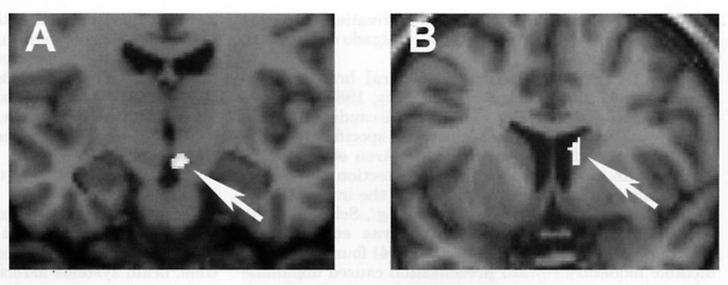

Это напоминает состояние абстиненции (синдром отмены), в котором находится человек с зависимостью, когда перестает принимать стимуляторы. Исследование, проведенное все той же Хелен Фишер и ее коллегами в 2010 году, , что после недавнего расставания у людей, тяжело переживающих разрыв, в системе вознаграждения активируются те же зоны, что и употребляющих кокаин.